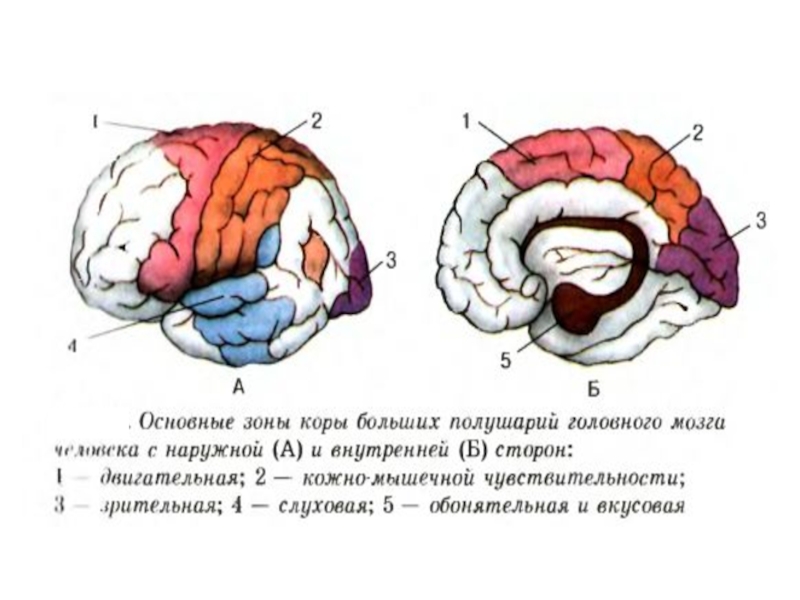

Схема чувствительных зон новой коры мозга